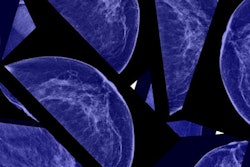

Measuring breast density with automated software might be a more precise tool for assessing breast cancer risk than visual measurements based on BI-RADS criteria, according to a new study published in the January issue of the American Journal of Roentgenology.

Researchers from Elizabeth Wende Breast Care (EWBC) found that the sensitivity of automated volumetric breast density assessment was more similar to that of mammography than visual calculations of density based on BI-RADS assessment categories (AJR, January 2017, Vol. 208:1, pp. 222-227).

The team led by Dr. Stamatia Destounis included 771 breast cancers diagnosed at EWBC between 2009 and 2012. Of these, 652 were detected on screening and 119 were interval cancers. The group assessed breast density using both BI-RADS categories and VolparaDensity software from Volpara Solutions. The software generates a measurement of breast density as Volpara Density Grades, which correspond with BI-RADS density categories.

Destounis and colleagues found that overall mammographic sensitivity was 85%. Across visual BI-RADS categories, mammographic sensitivity was 82% for fatty breasts, 90% for breasts with scattered fibroglandular tissue, 84% for heterogeneously dense breasts, and 66% for extremely dense breasts. Using VolparaDensity categories, mammographic sensitivity was 95% for fatty breasts, 89% for breasts with scattered fibroglandular tissue, 83% for heterogeneously dense breasts, and 65% for extremely dense breasts.

"For women with dense breasts, there is a large range in sensitivity that is not being captured using the visual BI-RADS system which could impact the selection of women who would most likely benefit from supplemental imaging," Destounis said in a statement released by EWBC.